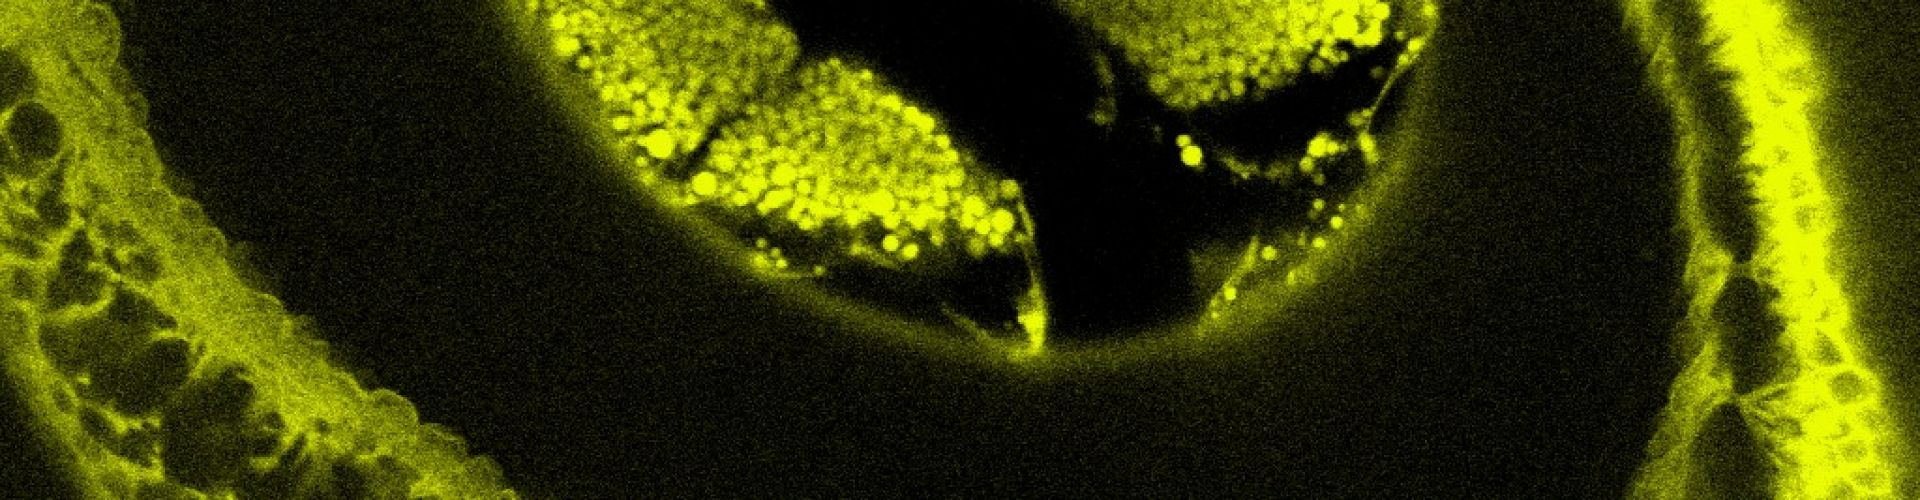

Fotografie této firmy